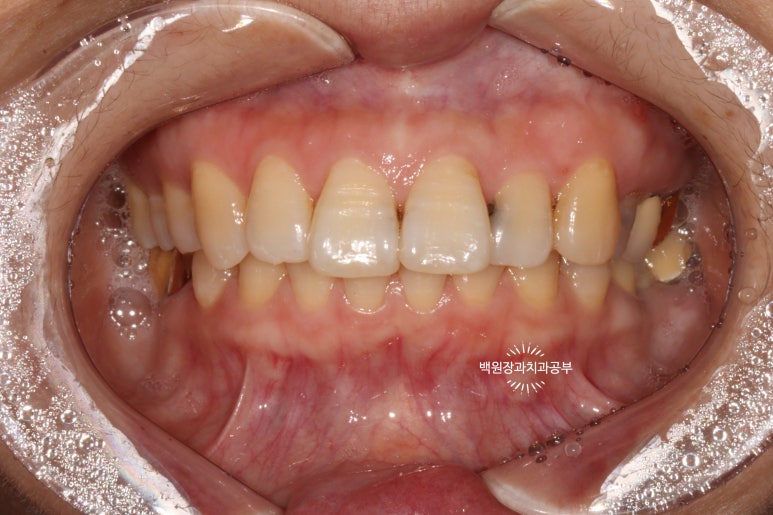

서론이 길었네요. 60대 여자 환자분이시고 위 앞니 사이사이에 있는 인접면 충치 치료차 내원하셨습니다.

정면을 보면, 치아 사이사이에 있는 충치가 얼핏 보이실거에요!

하얀것은 치아고 까만것은 충치라는걸 유치원생도 다 구분할 수 있을거에요. ㅎㅎㅎ

위턱 앞니의 사이사이마다 인접면 충치가 보이네요...

치료 전과 치료 후를 쉽게 비교하실 수 있도록, 치료 직전 찍어놓은 사진이에요.

상악 중절치와 측절치 그리고 견치에 옆면 모두에 충치가 있습니다.